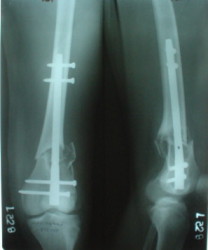

The mobilisation of knee is started immediately from the second day. Weight bearing is permitted as in any other interlocked nailing. That is, Toe touch to start with and within four days, partial to in another two weeks, full weight bearing. Of course that is assuming that the correct size nail has been used. Up to 70 kg body weight, 11no will be good enough and 12mm if more.Usually at the 1st followup, at 6 weeks time, they have full flexion..I

Enclosing a recent intraop picture